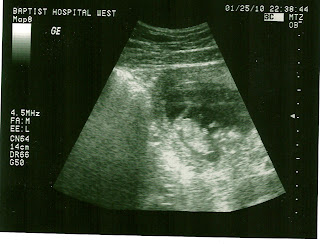

Here is one shot we got... it's my favorite because you can see its little hands and feet all sticking up! Head is at the bottom, hands and feet in the air.